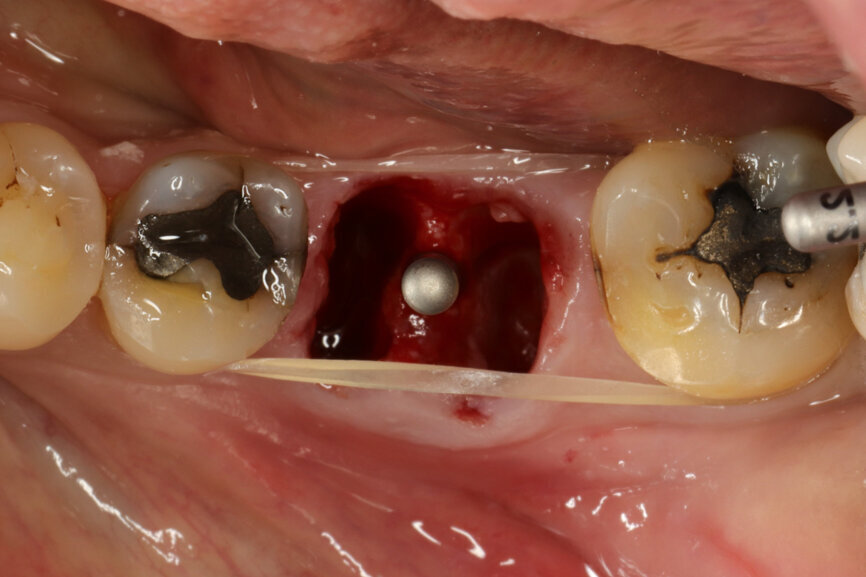

Fig. 5: Socket dimensions preserved.

It was possible to verify solid interradicular bone availability (Fig. 5), extending further the limits of the root apices and allowing for a centrally oriented osteotomy. The implant bed preparation started with the use of a needle drill at 800 rpm, followed by the ⌀ 2.2 mm and ⌀ 2.8 mm drills (Figs. 6–10). The implant was placed with the use of ratchet and torque control, reaching the desired final position at a 50 N cm torque value (Figs. 11–13). The socket was then augmented with bovine-derived bone substitute impregnated with advanced platelet-rich fibrin (A-PRF) and finalised with sutures to keep the A-PRF application immobile, and a 3 mm healing abutment was placed (Figs. 14–17).